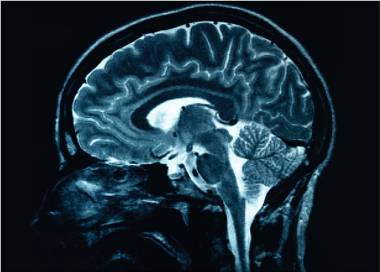

Cel mai tânăr pacient cu Alzheimer din lume, diagnosticat la 19 ani / Nu are mutații genetice sau antecedente familiale care să explice apariția atât de timpurie a bolii

Cel mai tânăr pacient cu Alzheimer din lume este un băiat de 19 ani din China. A început să aibă probleme de memorie la vârsta de 17 ani, transmite Mediafax. Nu are nicio mutație genetică cunoscută sau antecedente familiale care să explice apariția extrem de timpurie a bolii. Boala Alzheimer este asociată în mod tradițional […]